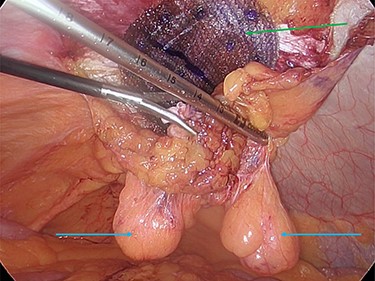

The hernia neck was closed with a 2-0 V-loc© suture (Fig. 5a and b), and a preperitoneal prolene mesh applied. The mesh was secured to the abdominal wall with an absorbable tack fixation device. The mesh was then reperitonealized with absorbable tackers (Fig. 6).

(a and b) Intracorporeal suturing of the hernia neck (green arrow) and closure of the hernial defect.

Preperitoneal mesh insertion (green arrow) and visible parietal peritoneal lipomas (blue arrows).